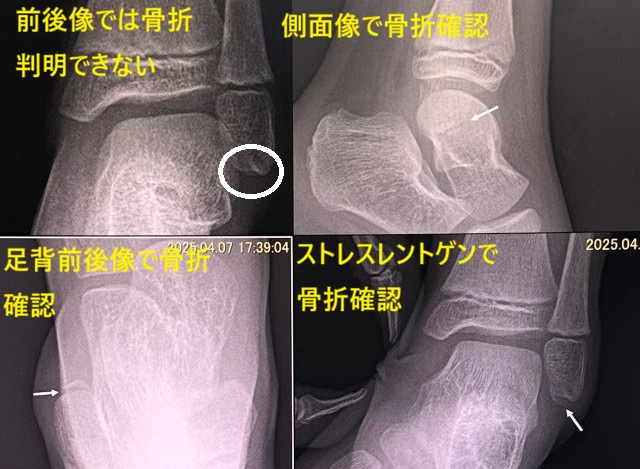

剥離骨折のあるタイプ

外果剥離骨折と内果剥離骨折などあるタイプです。

大半が内反(内返し)が強制されて起こる外果剥離骨折です。

診断の際に多方向撮影やストレスレントゲン撮影で確認されることが多々あります。時に外反(外返し)が強制されて起こる内果剥離骨折も経験します。

また陳旧性外果剥離骨折(過去に骨折したタイプ)もありますので注意深く観察が必要です。まれに